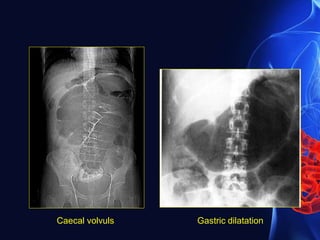

 Caecal volvulus

• Associated with degree of malrotation

• Accounts for less than 2% of adult intestinal obstruction

• Age -30-60 years

Diagnosis

• Pole of the caecum and the appendix lie in LUQ(50%)

• Caecum twists in axial plane and lies in the central part

on right half of abdomen(50%)

• One or two haustral markings can usually be identified

• Seen as large gas filled or fluid filled viscus

• Identification of adjacent gas filled appendix confirms the

• Left half of colon is usually collapsed

Caecal volvuls Gastric dilatation